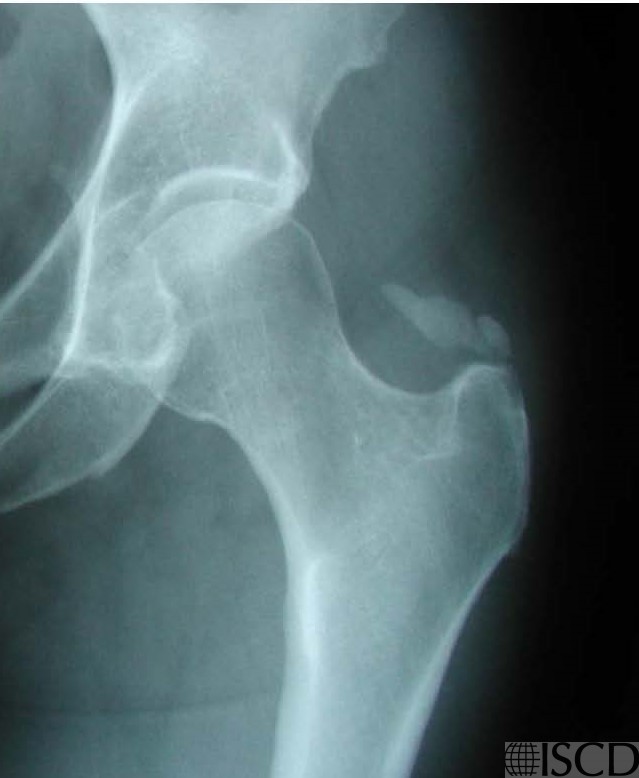

Calcific tendonitis is seen on this GE Healthcare left hip image.

The accompanying radiograph demonstrated calcific tendonitis/bursitis.

Calcific tendonitis/bursitis is seen in this left GE Healthcare image and accompanying radiograph.